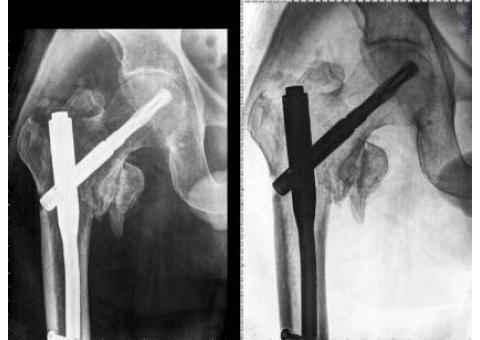

ارایه ی خدمات رادیولوژی و سونوگرافی در منزل به صورت شبانه روزی و بدون تعطیلی در کلیه ی نقاط کشور . تیم تصویر برداری گروه پزشکی امید متشکل از بهترین پزشکان و کارشناسان فارغ التحصیل از دانشگاه های برتر کشور هستند. امروزه با توجه به ترافیک سرسام اور به ویژه در کلانشهرها و همچنین شیوع ویروس کرونا و همچنین هزینه های بالای امبولانس هم از نظر اقتصادی و هم از نظر صرفه جویی در زمان و از همه مهمتر برای پیشگیری از ابتلای به بیماری کرونا، استفاده و بهرمند شدن از خدمات پزشکی و تصویر برداری پرتابل در منزل بیش از پیش همه گیر شده است. و تیم پزشکی امید مفتخر است که با ۱۴سال سابقه در ارایه ی خدمات رادیولوژی پرتابل در منزل و بکارگیری متخصصین بنام کشور و استفاده از بروزترین تجهیزات قابل حمل، در این ایام که پاندمی کرونا نفس سلامتی را تهدید میکند، در کنار هم میهنان عزیز بتواند گرهی از کار خانواده هایی که بیمار در منزل دارند را باز کند. کافیست با ما تماس بگیرید،۰۹۳۹۹۵۴۵۰۸۸ - ۰۹۱۰۵۵۴۵۷۹۰ - ۰۲۱۹۱۰۱۶۹۲۳